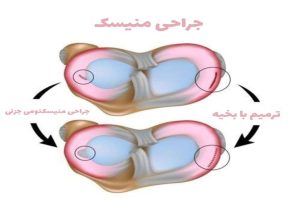

درمان جراحی پارگی منیسک

اگر علیرغم درمان های محافظه کارانه و غیر جراحی ، زانوی شما همچنان دردناک است یا اگر زانوی شما قفل می شود، پزشک ممکن است جراحی را توصیه کند. گاهی اوقات امکان ترمیم پارگی منیسک، به خصوص در کودکان و بزرگسالان وجود دارد.

اگر پارگی بزرگ و ناپایدار باشد یا باعث ایجاد علائم قفل شدن زانو شود، پزشک شما عمل جراحی آرتروسکوپی را انجام خواهد داد. آنها یک دوربین کوچک را از طریق یک بریدگی کوچک در زانو وارد می کنند و به آنها اجازه می دهد تا داخل زانو را ببینند. سپس تعدادی ابزار جراحی را از طریق دو یا سه برش کوچک دیگر وارد میکنند تا پارگی را اصلاح یا ترمیم کنند درواقع تکه های بافت منیسک پاره شده را طی عمل جراحی ترمیم میشوند (به هم دوخته شده)، زمان رسین به بهبودی کامل طولانی تر است، زیرا باید منتظر بمانید تا منیسک بهبود یابد. ممکن است در طول ریکاوری به بریس نیاز داشته باشید. این روش معمولاً بسیار ساده است و اغلب می توانید همان روز به خانه بروید (تصویر شماره۹ ).

تصویر شماره ۹ : جراحی منیسک زانو

اگر جراحی منیسکتومی جزیی باشد شامل برش در ناحیه پاره شده، برداشتن قطعه آسیب دیده منیسک و صاف کردن محل آسیب است، دوره نقاهت کوتاه است. در منیسکتومی کامل کل منیسک برداشته میشود (تصویر شماره ۱۰ ).

تصویر شماره ۱۰ : جراحی منیسک